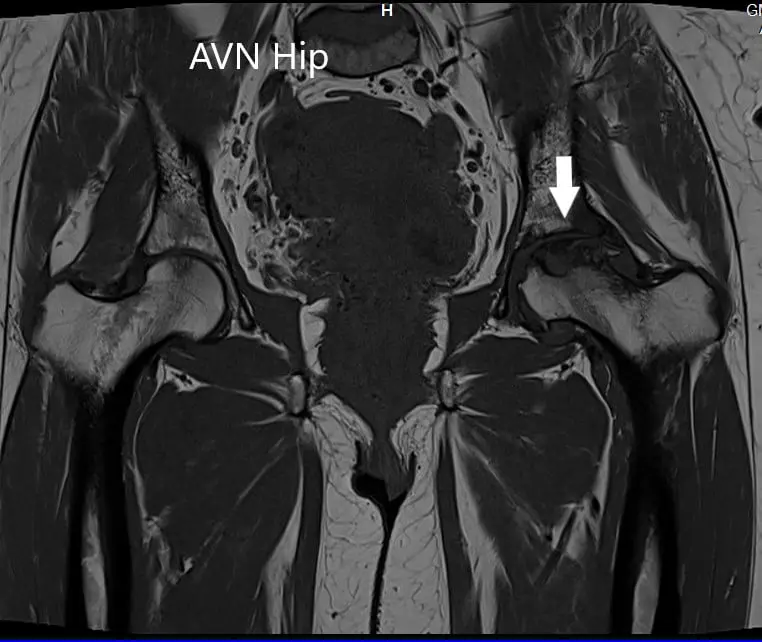

An MRI was obtained which showed altered signal intensity in both T1WI and T2WI. There was a subtle collapse of the left femoral head. A serpiginous hyperintense line was seen on T2WI demarcating an area of osteonecrosis in the left femoral head. This area involved the lateral and medial compartment and covered more than 50% of the surface area of the head.

Secondary osteoarthritic changes were visualized in the form of reduction of anterosuperior joint space and osteophyte formation. A small amount of fluid was seen in the joint cavity.

T1WI image of MRI showing the coronal section.